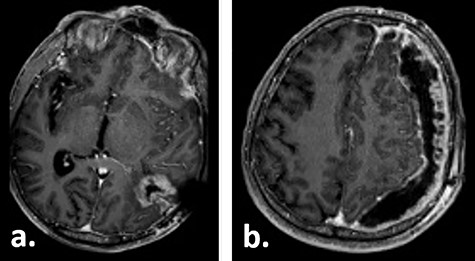

A 67-year-old male patient presented at a local hospital with progressive fatigue, memory and concentration loss, right-sided neglect and weakness as well as gait disturbance. A cerebral MRI scan depicted an inhomogeneous contrast-enhancing, left temporo–parieto–occipital intracerebral tumour invading the trigonum of the left lateral ventricle. The tumour was resected subtotally under 5-ALA fluorescence with a small remnant infiltrating the trigonum of the left lateral ventricle, which was opened intraoperatively (Fig. 1). Histologically, glioblastoma multiforme, WHO IV°, was diagnosed. No molecular analysis was performed.

Gadolinium-enhanced T1-weighted axial MRI of the patient preoperatively (a) and 1 day after the tumour resection (b, c).